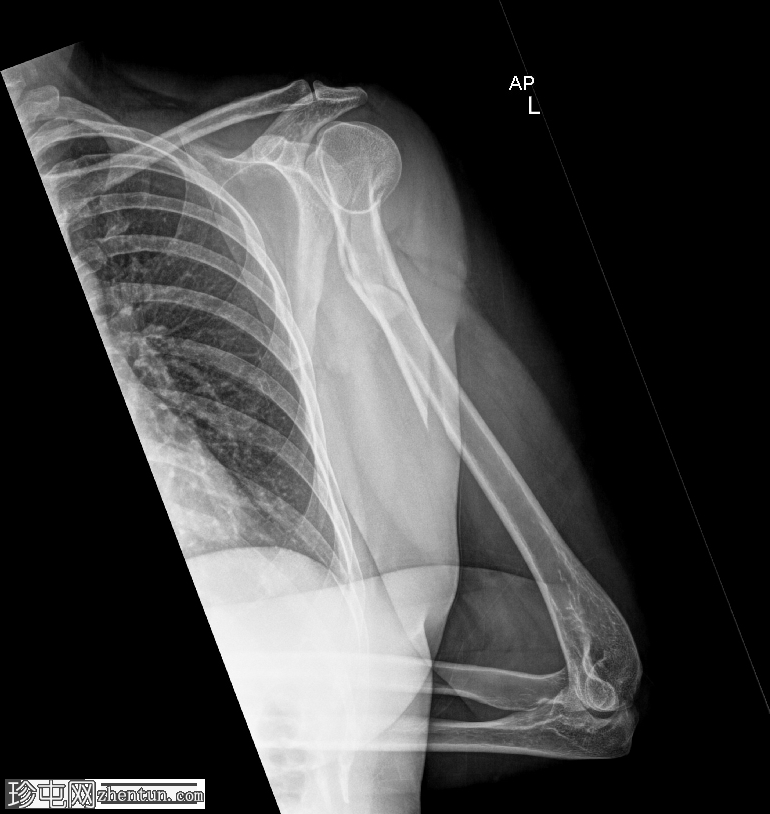

X线片

2.png

斜位

肱骨近端粉碎性移位骨折,累及骨干近端半部、外科颈,并延伸至大结节。

肱骨头在肩关节内向下半脱位,肩峰肱骨间距增大。